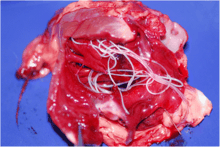

Jackals in southwestern Tajikistan have been recorded to carry 16 species of parasitic cestodes, roundworms and acanthocephalans, these being Sparganum mansoni, Diphyllobothrium mansonoides, Taenia hydatigena, T. pisiformis, T. ovis, Hydatigera taeniaeformis, Diphylidium caninum, Mesocestoides lineatus, Ancylostoma caninum, Uncinaria stenocephala, Dioctophyma renale, Toxocara canis, Toxascaris leonina, Dracunculus medinensis, Filariata and Macracanthorhynchus catulinum. Jackals infected with D. medinensis can infect water bodies with their eggs, and cause dracunculiasis in people who drink from them. Jackals may also play a large part in spreading coenurosis in sheep and cattle, and canine distemper in dogs.[54] During July 2006, a jackal in Romania was found to be carrying Trichinella britovi.[55] Jackals consuming fish and molluscs can be infected with metagonimiasis, which was recently diagnosed in a male jackal from northeastern Italy.[56]